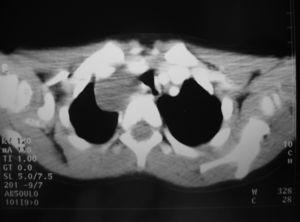

Entre las pruebas complementarias realizadas el electrocardiograma, hemograma y bioquímica no presentaban alteraciones. En la radiografía de tórax se observaba una masa de contornos lobulados, bien delimitada en mediastino superior que originaba ensanchamiento bilateral; en la tomografía computarizada (TC) torácica con contraste (fig. 2) se visualizaba una masa de densidad agua, sin verse adenopatías, la lesión se consideró compatible con quiste de duplicación. En el parénquima pulmonar se observaba una hiperaireación del lóbulo medio con imágenes quísticas alternando con parénquima normal que podría corresponder a malformación adenomatoidea quística o enfisema lobular congénito (fig. 3). El tránsito digestivo superior mostraba una compresión en el tercio inferior de esófago por una masa paratraqueal derecha y en la esofagoscopia no se vio comunicación con la luz esofágica.

Figura 3.TC torácica: hiperaireación del lóbulo medio con imágenes quísticas alternando con parénquima normal.